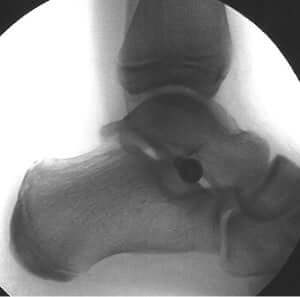

X-rays to determine the severity of the condition. Radiographs can also help rule out other conditions.

A simple, minimally invasive Subtalar Joint Arthroereisis implant can be very beneficial.